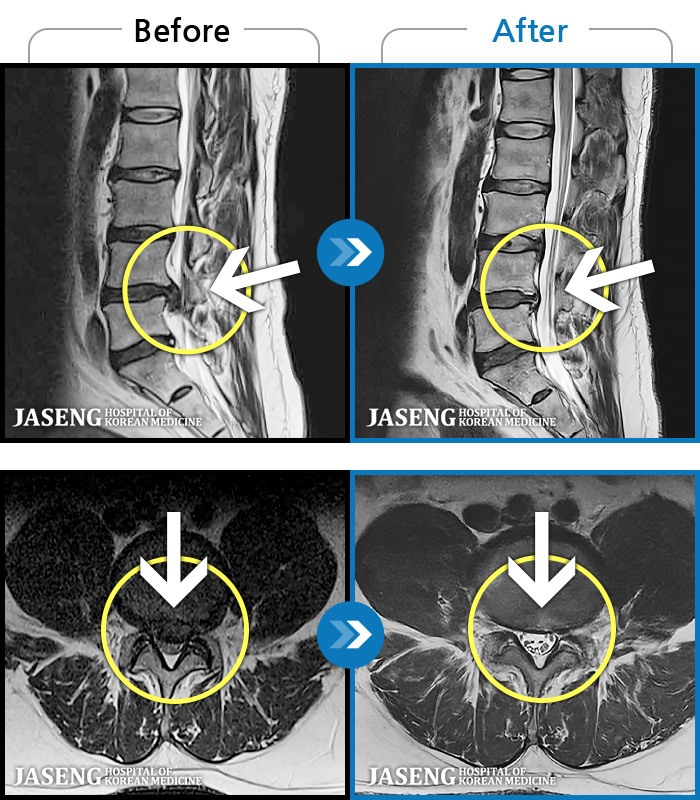

1,240 MRI ũ ʸ Ȯϼ.

MRI ġ

Ƹ ϰ ־.